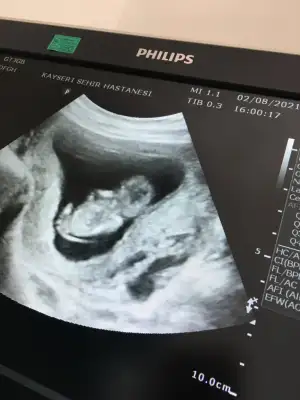

Kizim oluyor hayirlisiyla insallahEvet burada bacak arası boş görünüyor sağlıkla gelsin prensesdiğer usg de çıkıntısı vardı

renklide nub ölçümü olmuyor bakalım nolcak